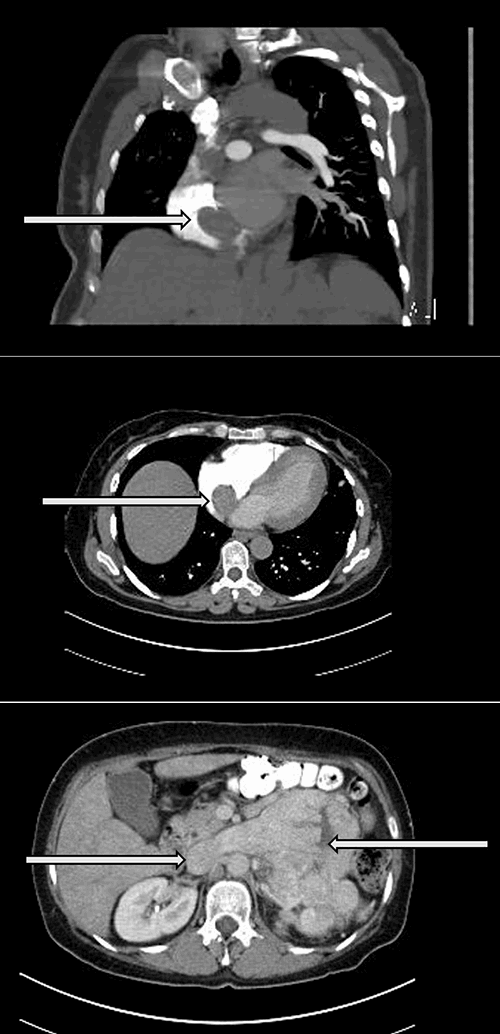

A computed tomography of the chest/abdomen/pelvis showed a large mass concerning for malignancy measuring 12.3 x 9.7cm, and arising from the left upper quadrant and displacing the left kidney inferiorly, with tumor extension into the left renal vein, up the IVC nearly obstructing it and into the right atrium (Figure 2).

Figure 2: Computed tomography of the chest and abdomen demonstrating a tumor extending into the inferior vena cava and the right atrium. (A) Coronal view of intracardiac tumor (arrow) (B) Axial view of the intracardiac tumor (arrow) (C) Axial view of the left adrenal mass with tumor extension into the left renal vein and IVC (arrows)